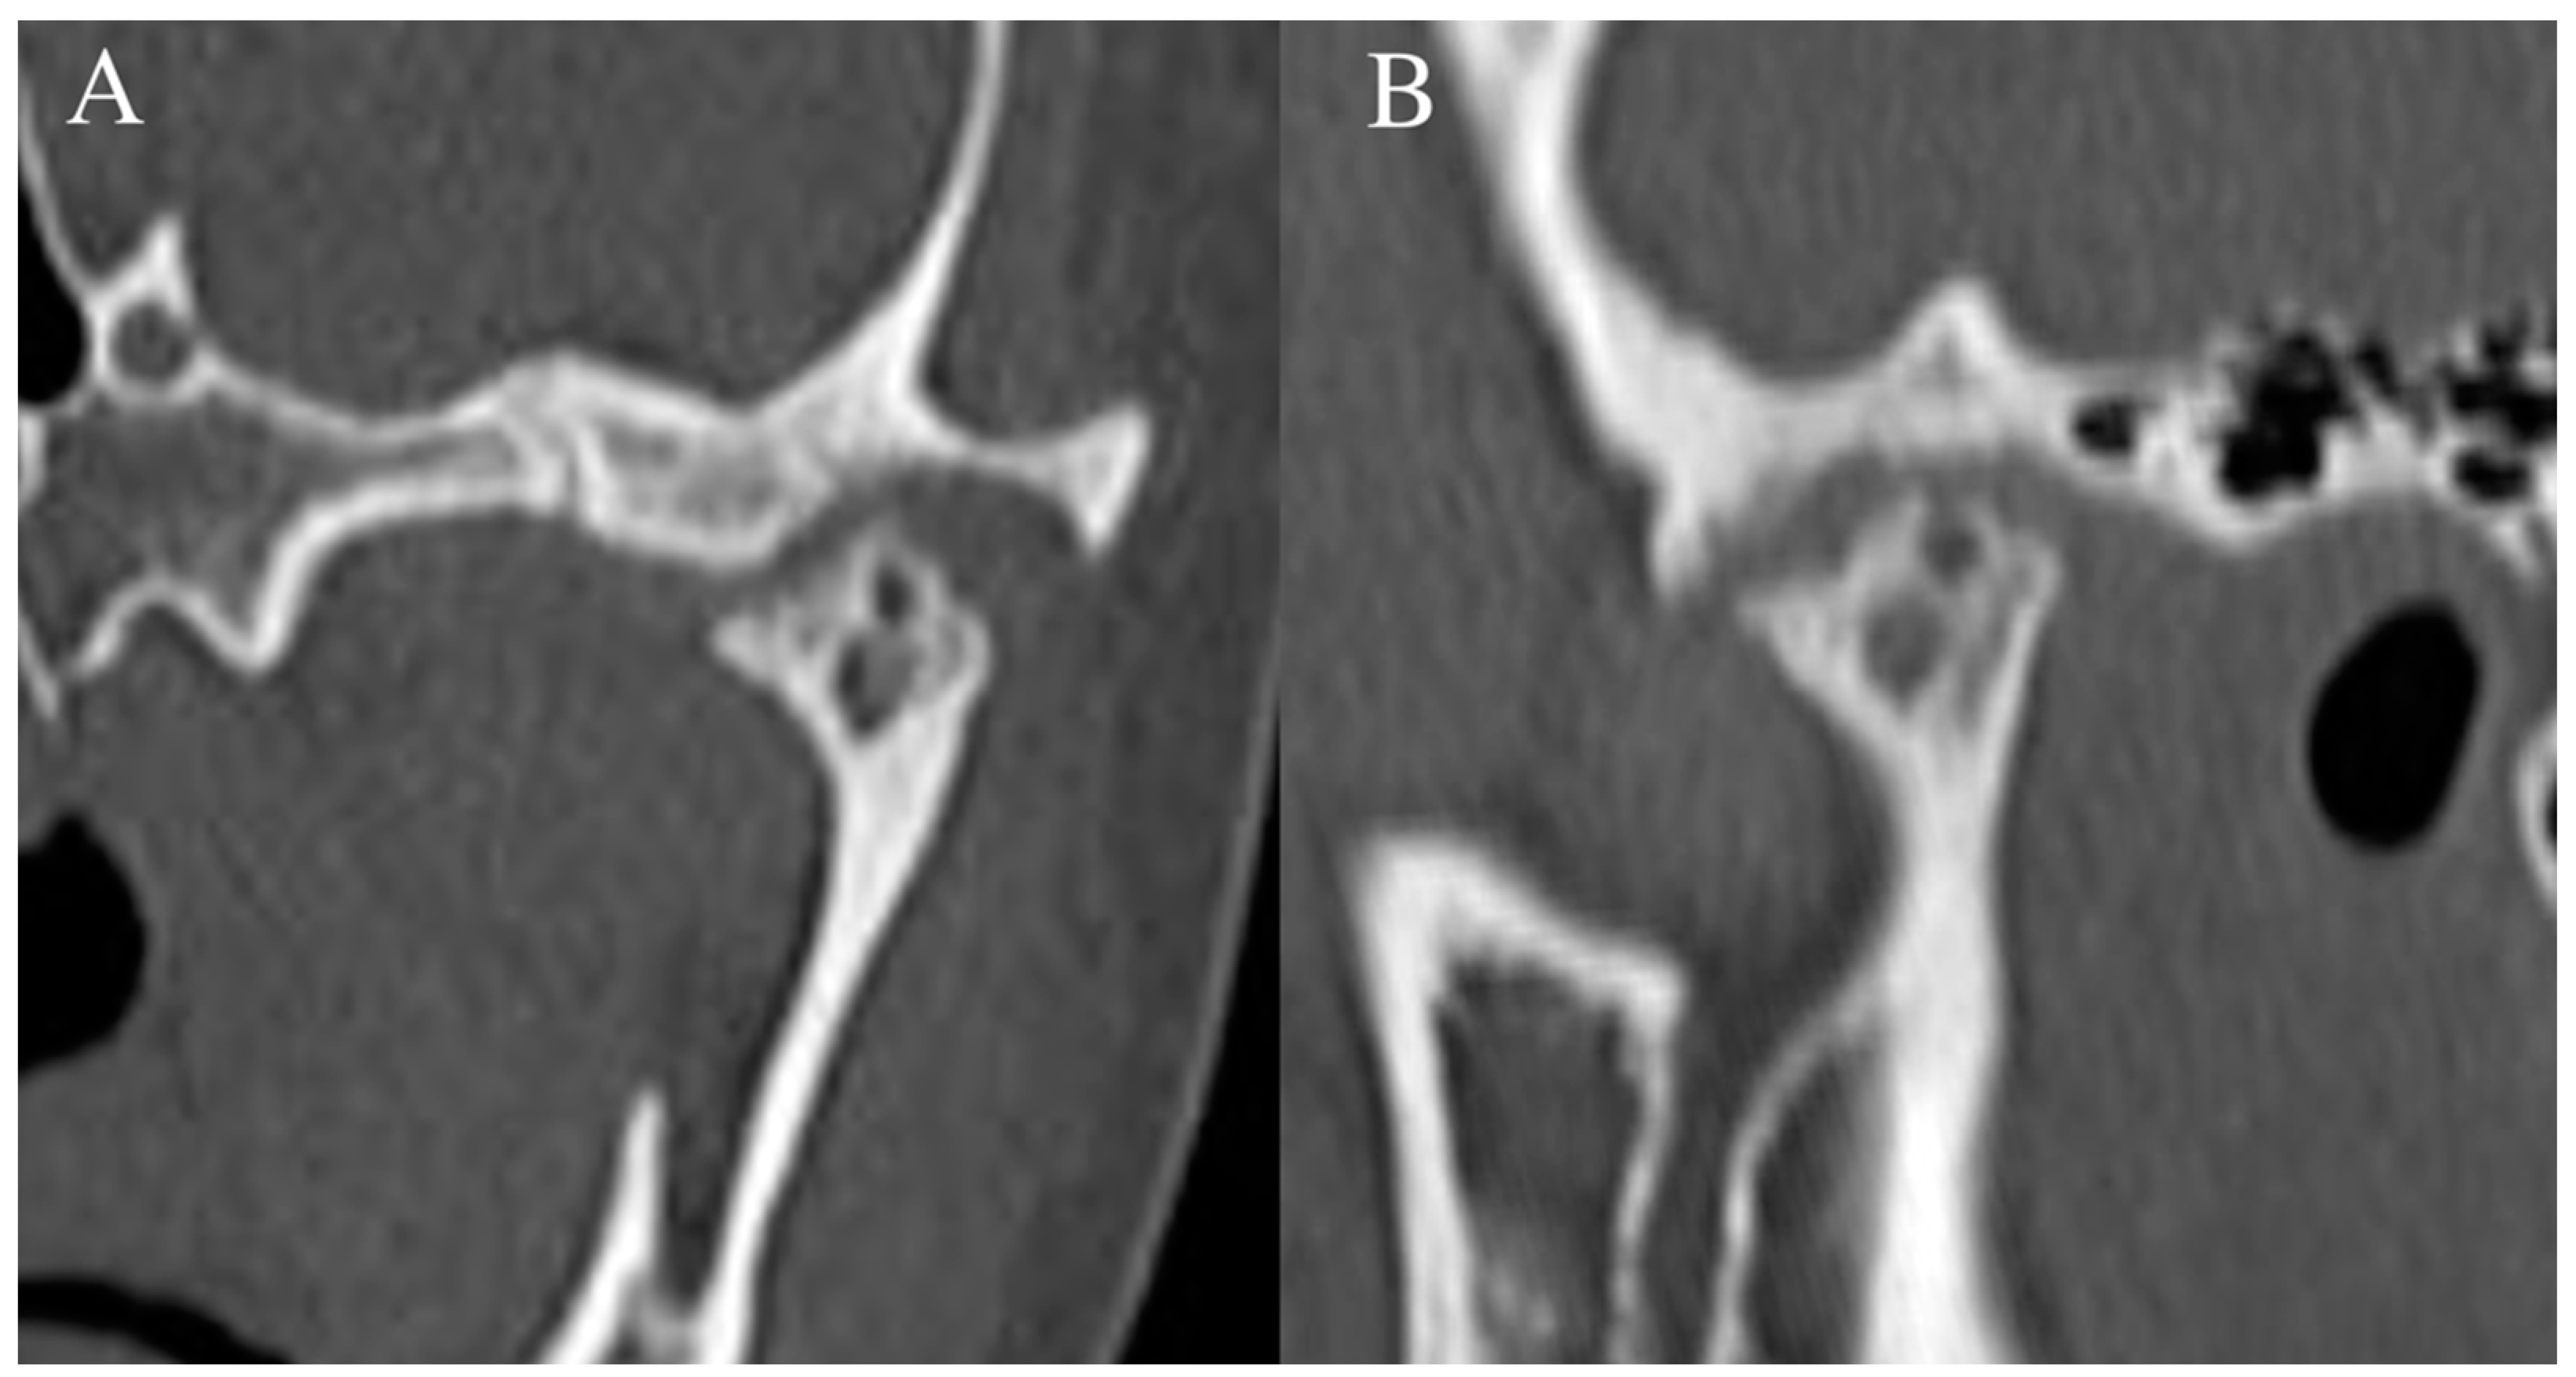

Figure 2. Temporomandibular joint radiographs. Axiolateral TMJ views in the closed mouth (A) and open mouth (B) positions demonstrate the normal location of the mandibular condyle within the mandibular fossa (black arrow) and normal condylar rotation and anterior translation (white arrow), respectively.